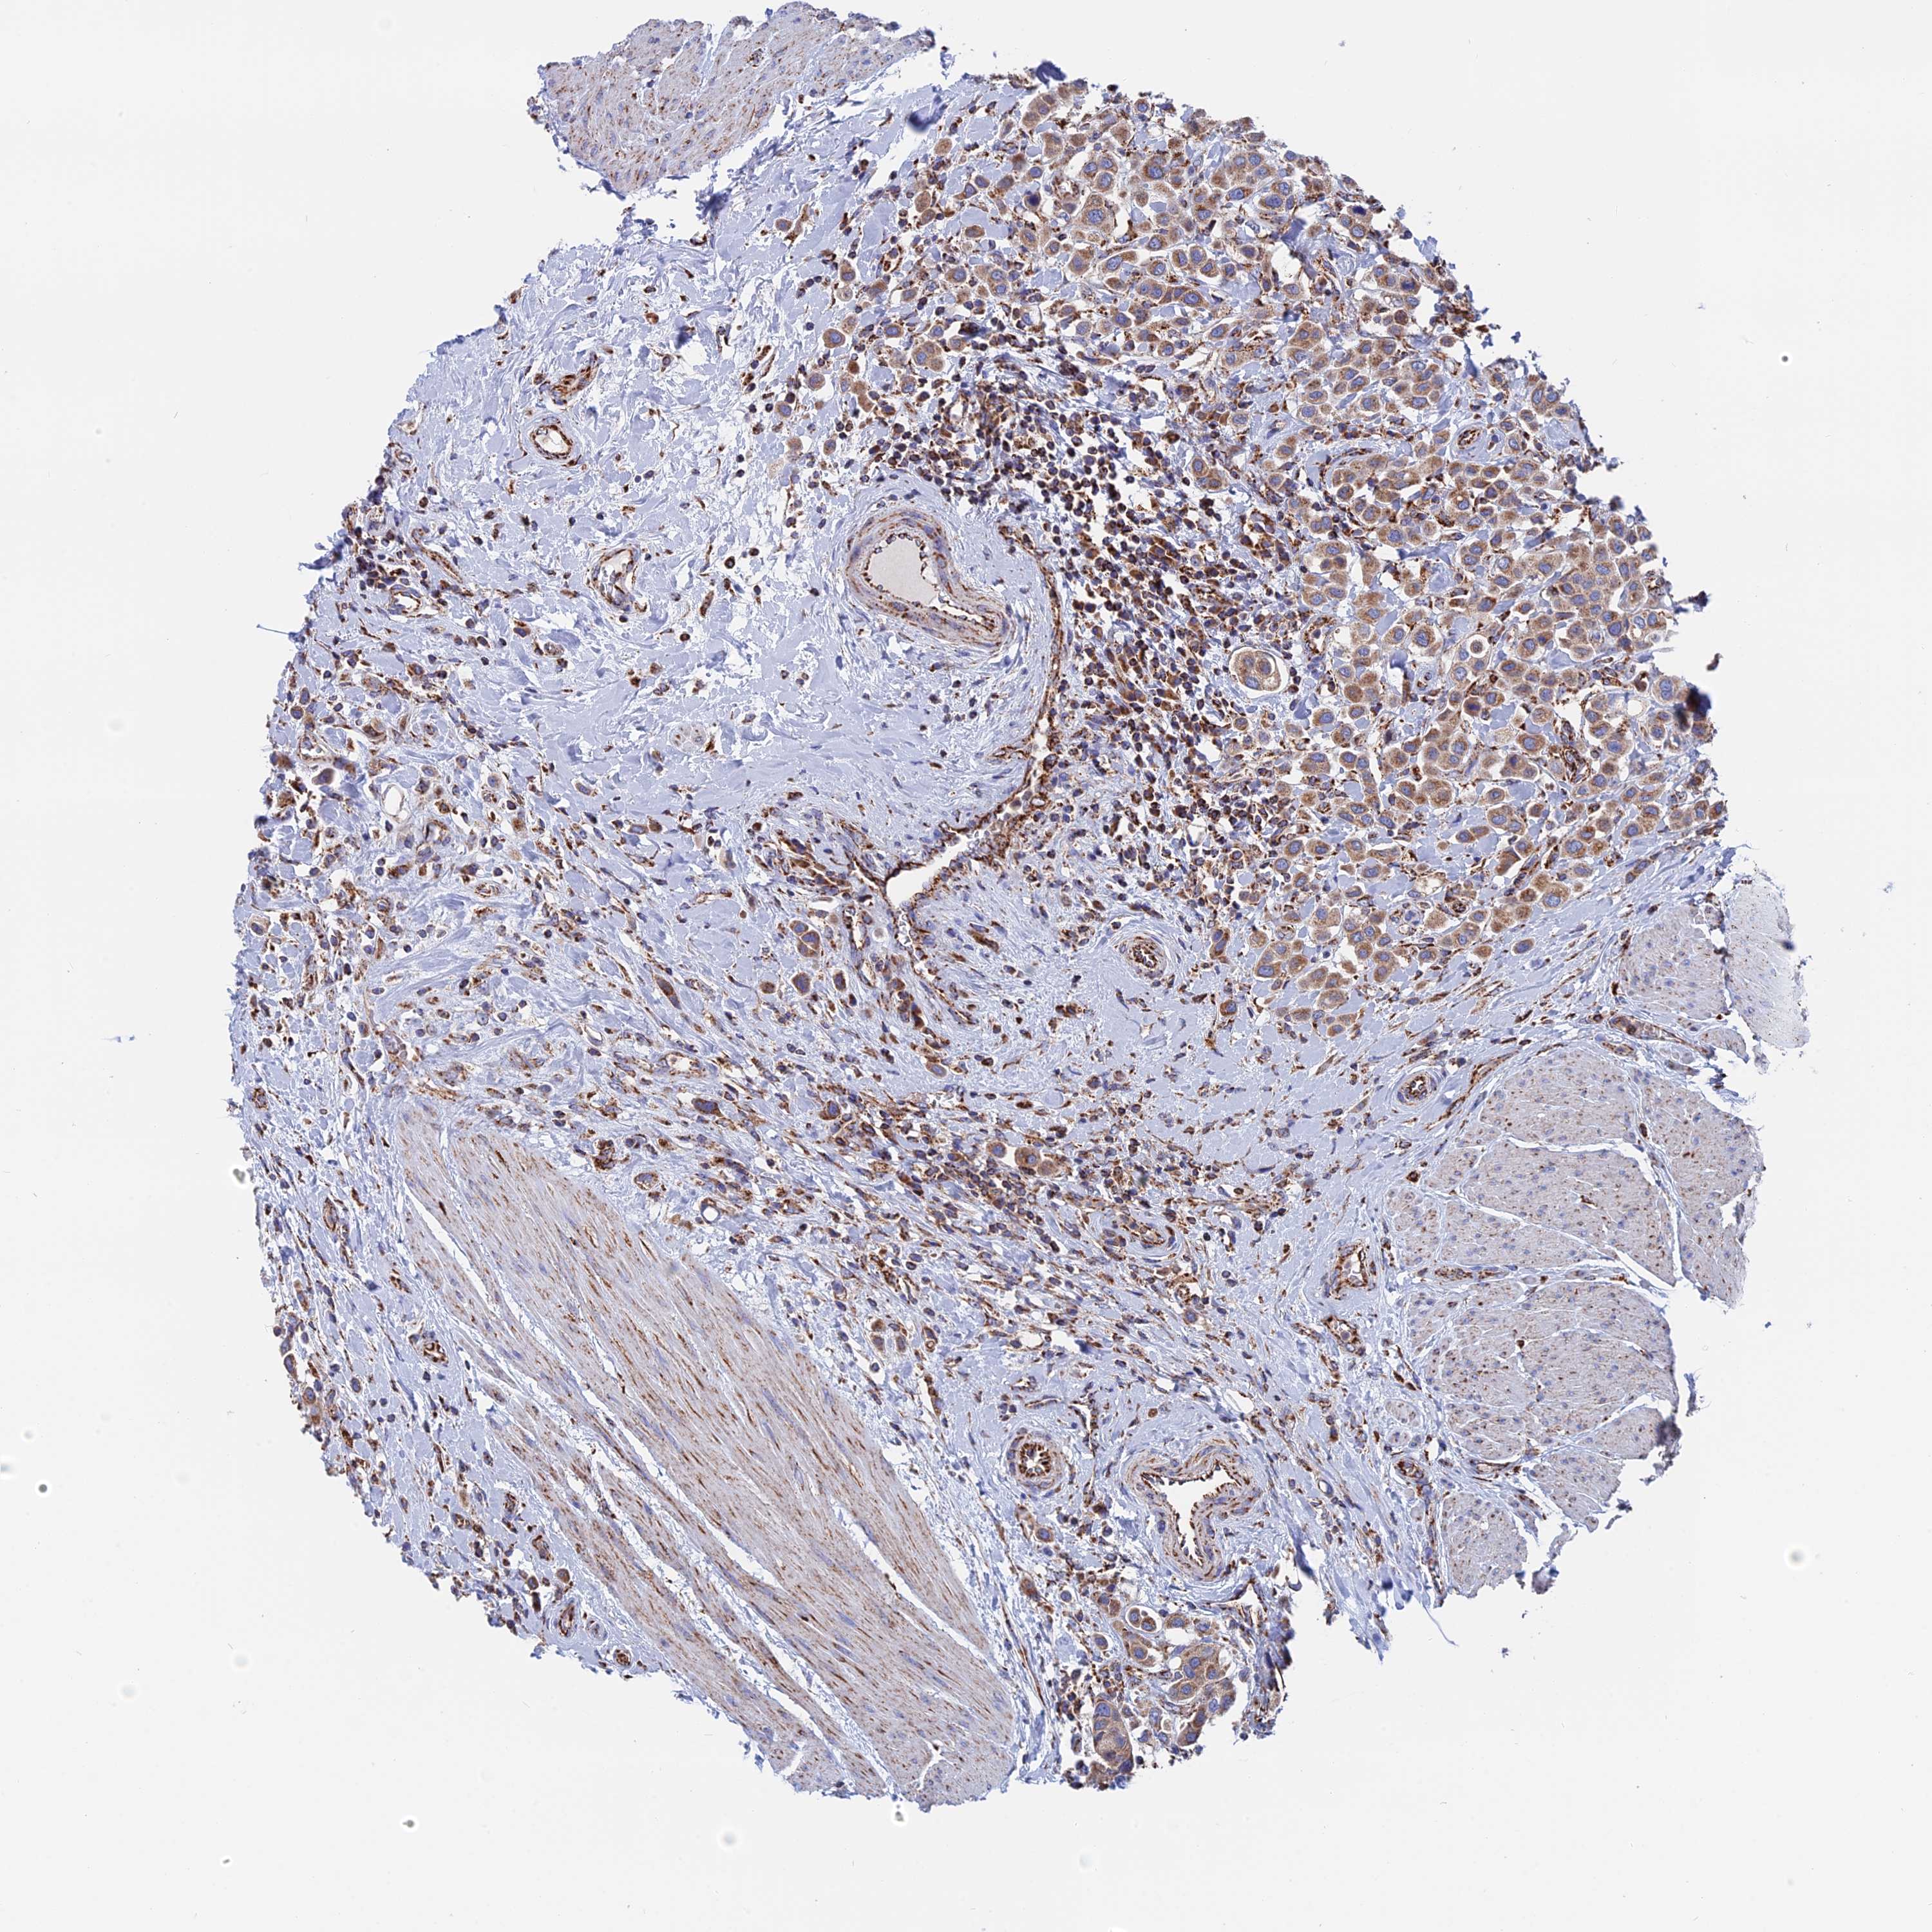

UROTHELIAL CANCER - Protein expressioni

A mouse-over function shows sample information and annotation data. Click on an image to view it in a full screen mode. Samples can be filtered based on level of antibody staining by selecting one or several of the following categories: high, medium, low and not detected. The assay and annotation is described here.

Antibody stainingi

Antibody staining in the annotated cell types in the current human tissue is reported as not detected, low, medium, or high, based on conventional immunohistochemistry profiling in selected tissues. This score is based on the combination of the staining intensity and fraction of stained cells.

Each image is clickable and will lead to virtual microscopy that enables deeper exploration of all samples and also displays staining intensity scores, fraction scores and subcellular localization as well as patient and tissue information for each sample.

Antibody HPA042629

Antibody HPA042838

Staining

High

Medium

Low

Not detected

Intensity

Strong

Moderate

Weak

Negative

Quantity

>75%

75%-25%

<25%

None

Location

Nuclear

Cytoplasmic/membranous

Cytoplasmic/membranous,nuclear

Urothelial carcinoma, Low grade